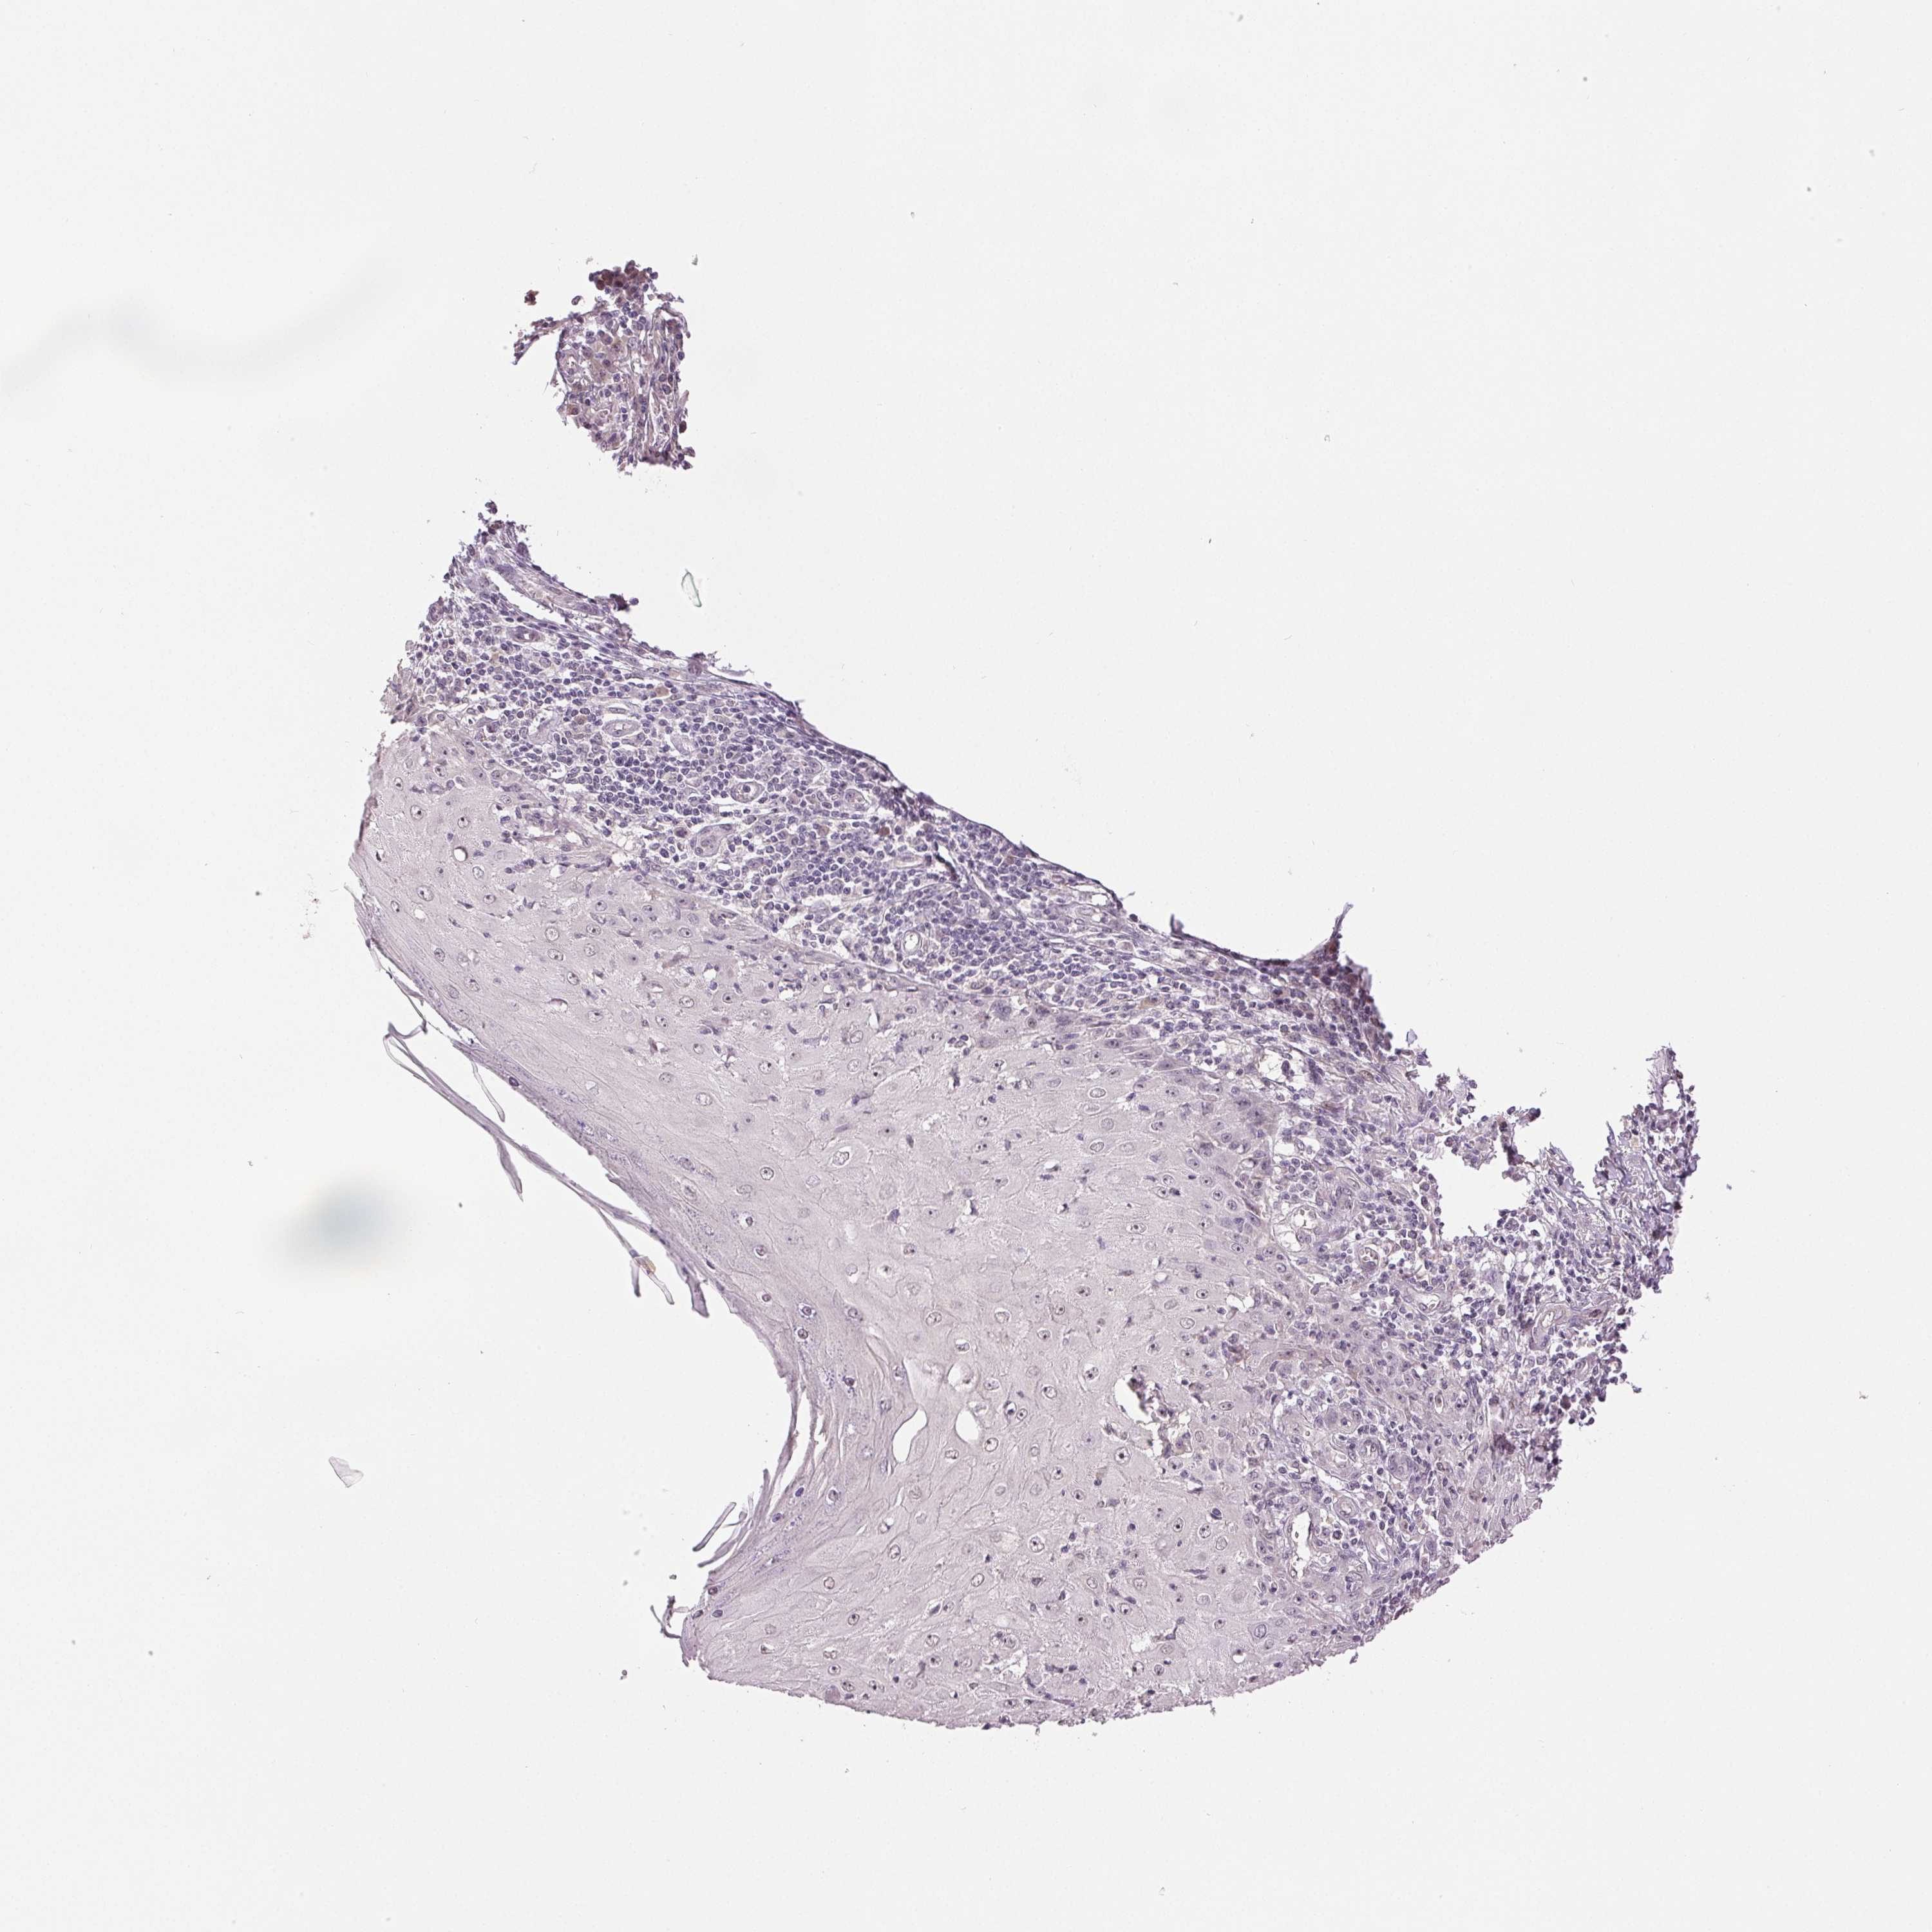

CANCER SKIN CANCER Show tissue menu

Basal cell and squamous cell cancer

SKIN CANCER - Protein expressioni

A mouse-over function shows sample information and annotation data. Click on an image to view it in a full screen mode. Samples can be filtered based on level of antibody staining by selecting one or several of the following categories: high, medium, low and not detected. The assay and annotation is described here.

Each image is clickable and will lead to virtual microscopy that enables deeper exploration of all samples and also displays staining intensity scores, fraction scores and subcellular localization as well as patient and tissue information for each sample.

Antibody HPA034743

Antibody HPA057910

Antibody CAB004275

Antibody CAB005334

Basal cell carcinoma

Squamous cell carcinoma, NOS